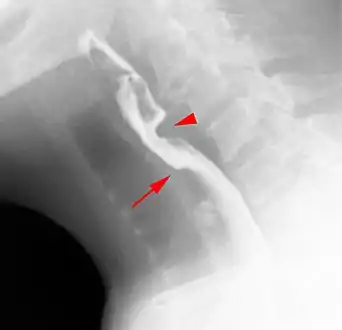

Web with "jet-phenomenon". Arrowhead on incomplete opening of the upper esophageal sphincter.

Esophageal webs are thin 2–3 mm (0.08–0.12 in) membranes of normal esophageal tissue consisting of mucosa and submucosa that can partially protrude/obstruct the esophagus. They can be congenital or acquired. Congenital webs commonly appear in the middle and inferior third of the esophagus, and they are more likely to be circumferential with a central or eccentric orifice. Acquired webs are much more common than congenital webs and typically appear in the cervical area (postcricoid).

The diagnostic test of choice is a barium swallow.